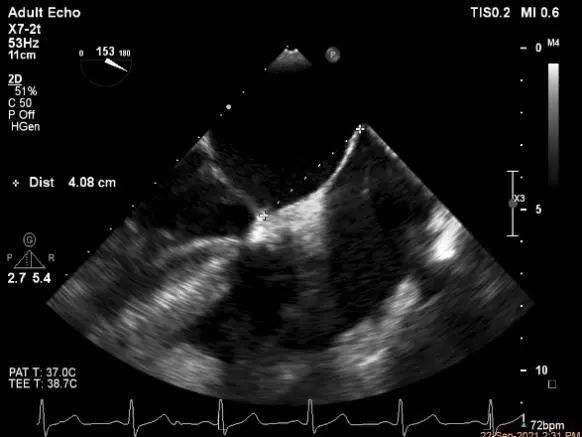

房间隔穿刺点选择

穿刺高度:4.08cm